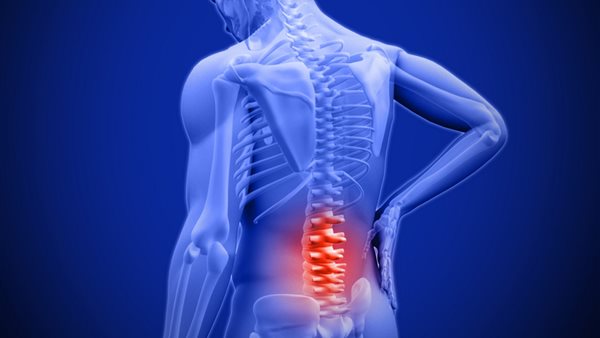

صعوبة الوقوف فترة طويلة.. ما أبرز أعراض قصور الفقرات؟

نستعرض لكم ضمن النقاط التالية أبرز التفاصيل حول قصور الفقرات وأسبابها واعراضها، حيث يتعرض الشخص للإصابة بألم شديد في الظهر يستدعي الفحص.

قال الدكتور خالد السيد، أستاذ جراحة المخ والأعصاب والعمود الفقري، إنه في حالة المعاناة من ألم شديد في الظهر، بجانب صعوبة في الوقوف فترات طويلة، من الممكن أن يرجع سببه لوجود قصور فقرات التي تتسبب في ضعف عمل فقرات العمود الفقري.

وذكر تفاصيل أكثر حول أعراض قصور الفقرات، حيث يرجع هذا لألم وانحناء غير طبيعي في الظهر، أو الإصابة بضعف عام في العضلات، والتعرض لتشنجات عضلية فلا يستطيع الشخص الوقوف فترات طويلة، فلا يجب تجاهل الأمر والتحدث مع الطبيب المعالج.